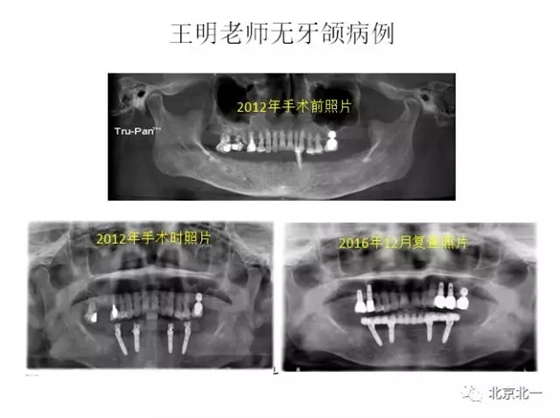

王明

擅長(zhǎng):種植外科,尤其專長(zhǎng)復(fù)雜牙種植,自體骨移植同期種植,上頜竇底內(nèi)外提升同期種植技術(shù),美學(xué)區(qū)種植技術(shù),即刻種植外科與即刻負(fù)重技術(shù),軟組織成形外科種植技術(shù)及全口無(wú)牙頜ALL-ON-FOUR技術(shù),種植并發(fā)癥和種植急癥處置等手術(shù)治療,從事口腔頜面外科,正頜外科、頜面部整形、微創(chuàng)拔牙,笑氣無(wú)痛舒適種植十余年。

畢業(yè)于中山大學(xué)光華口腔醫(yī)學(xué)院,擅長(zhǎng)各型牙列缺損缺失的種植義齒修復(fù)。